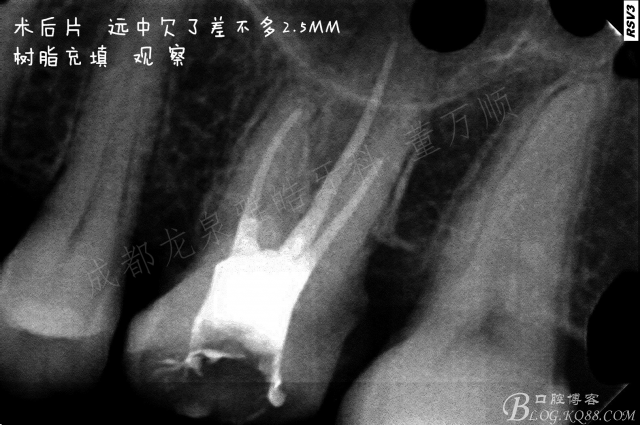

复查虽然术后反应消失了,但是 根管并没有做到标准的工作长度。相信我,我真的已经尽力了。